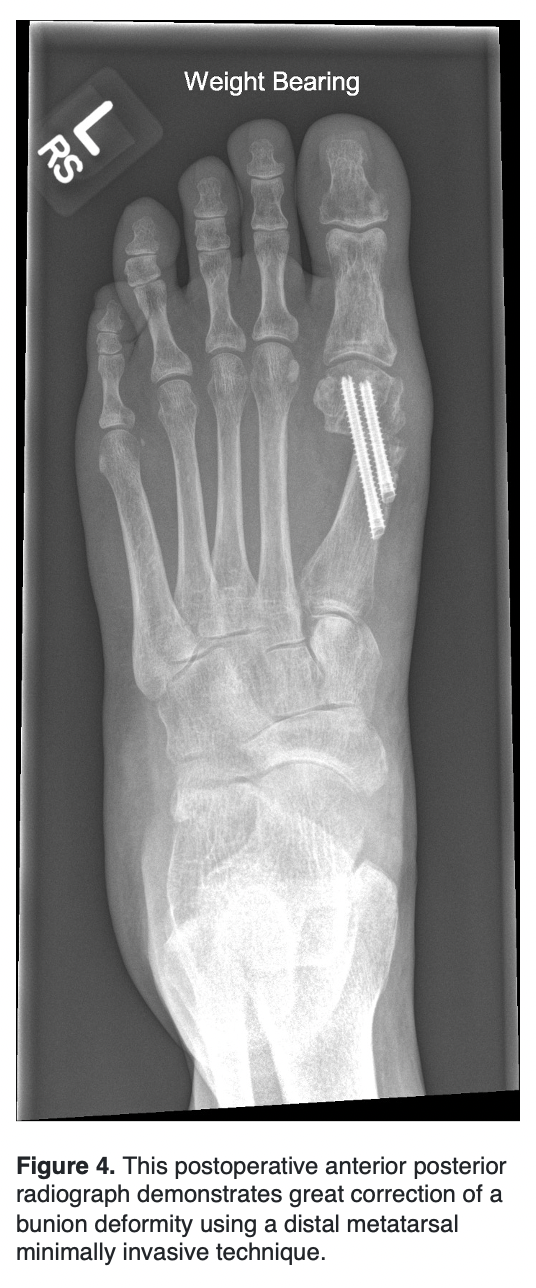

Minimally invasive bunion surgery is relatively new in the United States as the required burrs currently used were only approved by the FDA in 2017.10 Minimally invasive surgery involves little soft tissue dissection with bony correction while correcting the bunion deformity. Benefits of this technique include greater cosmesis results, minimal soft tissue dissection, shorter recovery period, and great patient satisfaction. It has been established that MIS technique is comparable to open technique in a randomized control trials comparing American Orthopedic Foot and Ankle Scores (AOFAS), visual analogue scale (VAS) and pain scores 5 years postoperatively.11 Opponents of this technique warn of complications such as nonunion, malunion, infection, and soft tissue irritation.12 Most of the soft tissue irritation occurs at the distal medial corner of the metatarsal shaft that is usually not shaved after performing the osteotomy, but the reported incidence is low.13

In 2016, Veronis and Redfern described correcting severe hallux valgus deformity with percutaneous procedures. The procedures described later became the currently used third generation of minimally invasive surgery for hallux valgus known as minimally invasive chevron-Akin (MICA). They focus heavily on evaluation of the width between the lateral first metatarsal head and medial second metatarsal head. They recommend 100% displacement as the maximum shift, which offers a reliable technique for all deformities. They report a large IM angle with a small metatarsal head as a limitation to this technique. For this pathology, they recommend a percutaneous basal closing wedge osteotomy. Veronis goes further suggesting that weight-bearing radiographs undervalue the instability of the tarsometatarsal (TMT) joint. He recommends a clinical squeeze test to assess the true potential IM angle. This allows the surgeon to determine the required lateral displacement of the metatarsal head to correct the deformity.15

In 2021, Lewis and colleagues looked at 53 feet with severe hallux who underwent percutaneous chevron and Akin (PECA) with a mean follow-up of 3 years.16 There was a statistically significant decrease in IM angle from 17.5 to 5.1 and HV angle from 44.1 to 11.5 degrees. All patients were satisfied with their outcome and 76.8% were highly satisfied. The recurrence rate was 7.5%. This recurrence rate is similar to open surgery for severe hallux valgus (2.7%-16%).17

In 2022, Lewis and colleagues looked at 106 patients prospectively undergoing third generation MICA with severe hallux valgus deformity. They looked at IM angles and HVA before and 6 weeks after surgery, as well as complications and clinical passive ranges of motion (PROM) 2 years following surgery. They found the mean IMA improved from 18.2 to 6.3 and the mean HVA improved from 45.3 to 10.9. They had a complication rate of 18.8% and screw removal rate of 5.6%. Two-year PROMs scores significantly improved for pain, walking and standing, and social interaction from 39.2 to 7.5, 38.2 to 5.9 and 48.6 to 5.5 respectively. The largest limitation to this study was the lack of long-term radiographic recurrence assessment.18

In conclusion, the Lapidus procedure continues to be at the forefront of larger bunion deformities as it significantly lowers the IM angle while correcting sagittal and frontal plane deformities. However, as MIS surgery continues to evolve with the technique, it too can correct in multiple planes in larger bunion deformities.